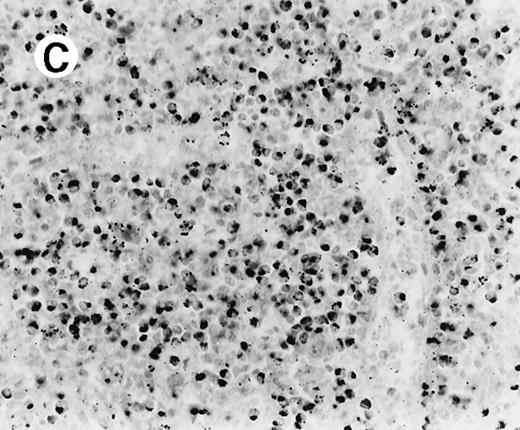

The immunophenotypic features and molecular data are summarized in Table 2. Immunophenotyping was performed on the spleen or liver or both in all cases. The infiltrate in all cases was composed predominantly of CD3+ T cells (Figure3A). CD20 stained attenuated residual B-cell areas in the spleen and only rare scattered B cells were identified within the liver (Figure 3B). Staining for CD4 and CD8 showed that the infiltrate was CD8+ in 2 cases (Figure4A), CD4+ in 2 cases (Figure5A), and in the remaining 2 cases CD4+ and CD8+ cells were noted in approximately equal numbers without clear subset predominance. CD4 highlighted the erythrophagocytic histiocytes (Figure 4B). The lymphocytes in all cases expressed βF1 and TIA-1+ (Figure 4C and D) and were CD56−.

Liver infiltrate from case 1.

The infiltrating lymphocytes are predominantly CD3+ T cells (panel A), with only rare L26+ B cells (panel B) (immunoperoxidase stained, hematoxylin counterstained, × 200).